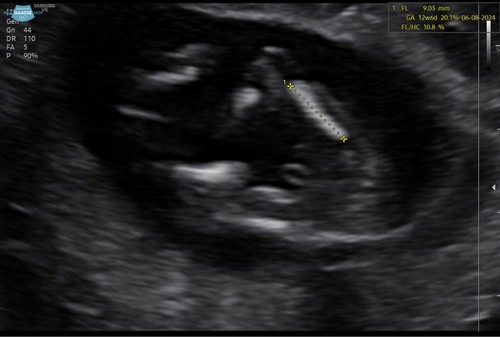

Kunnen jullie hier ook iets uithalen? Dit is namelijk ook vanaf ondergenomen …

2 jaar geleden